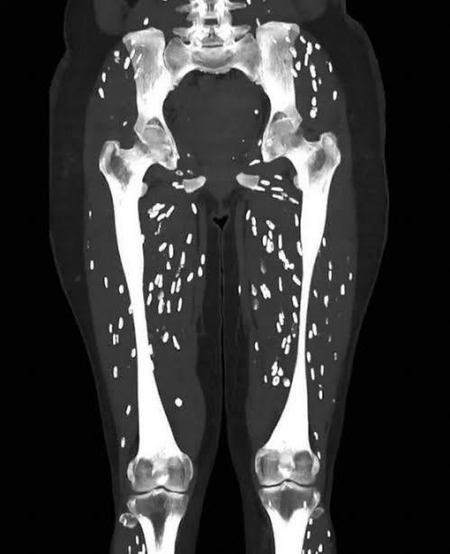

>>20

米国のある大学病院の医師が、まだ火が通っていない豚肉を食べて寄生虫に感染した患者のCT(コンピューター断層撮影)写真を公開し、注意を呼びかけた。

豚肉の寄生虫こわいよな